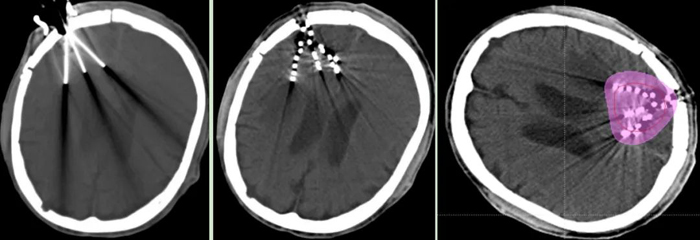

近日,我院腫瘤一科成功為一名腦膠質(zhì)母細胞瘤術(shù)后放療后復(fù)發(fā)患者,實施“CT引導(dǎo)腦部腫瘤125I放射性粒子植入術(shù)”。

經(jīng)腫瘤科、神經(jīng)外科、影像科等科室多學(xué)科討論,認為患者無再次手術(shù)及放療指征,決定行“CT引導(dǎo)125I放射性粒子植入術(shù)”。經(jīng)周密術(shù)前準(zhǔn)備,在神經(jīng)外科吳超副主任醫(yī)師協(xié)作下,張開賢主任帶領(lǐng)粒子治療團隊歷經(jīng)2個小時,在CT精準(zhǔn)引導(dǎo)下,成功完成了125I放射性粒子植入術(shù),現(xiàn)恢復(fù)良好。術(shù)后劑量驗證,達到術(shù)前計劃要求。

125I放射性粒子植入術(shù)屬于近距離放療的范疇,是在影像學(xué)引導(dǎo)下,精準(zhǔn)地將125I粒子植入在腫瘤病灶內(nèi),通過125I持續(xù)釋放低能量的γ射線,達到殺傷腫瘤細胞,控制腫瘤生長的目的。由于125I粒子釋放的γ射線能量小,射程短,劑量跌落快,因此,腫瘤病灶內(nèi)照射劑量很高(可達到外照射的2-3倍),而周圍正常組織劑量低,從而達到最大程度殺傷腫瘤細胞,而周圍正常組織不受損傷或輕微損傷的目的。目前已廣泛應(yīng)用于各部位腫瘤的治療,為惡性腫瘤的治療增加了一種新手段。